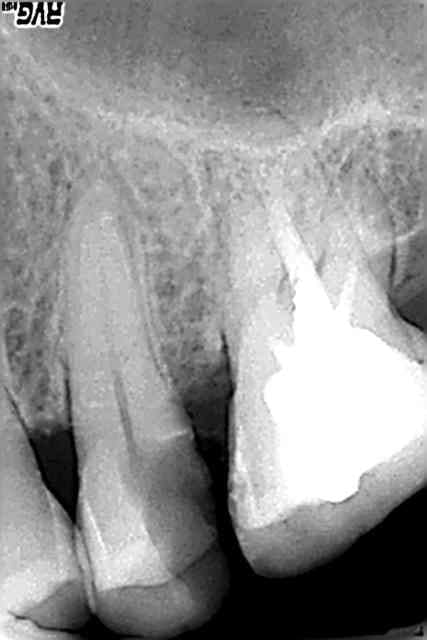

pendant que vous vous la pétez aux Seychelles (pffff) je me la pète au Termafil :-) héhé

c'est un bout de lime en mesial de la 46, a mi hauteur?

ben non, c'est le Thermafil....

hall,on s'en fiche:c'était là avant sur la radio de depart,elle a pu instrumenter et désinfecter au delà,l'obturation l'a englobé,dc tout va bien

Donc je ne la feliciterai pas pour etre passée a coté d'un morceau cassé.)

Désolé Doc , mais c'est Ploc qui veux pas... moi je voulais...;)